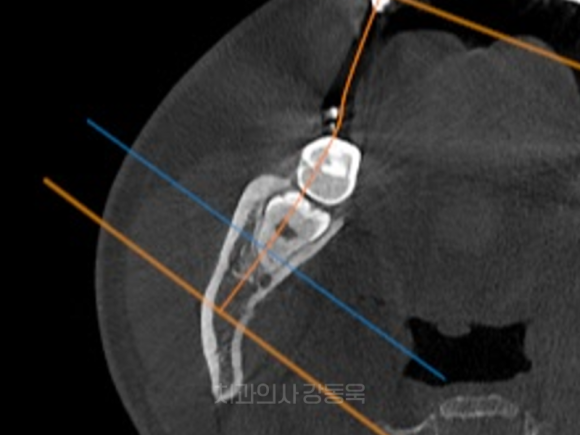

신경과 가까운 사랑니

일부 하악 사랑니 중에는,

신경과 매우 가까운 위치에 있습니다.

촬영일자: 2024.08.12

신경과 가까운 사랑니 이해를 위한 참고 사진입니다.

이런 경우에는 신중한 접근이 필요할 수 있는데요.

CT 이해를 돕기 위한 참고 사진입니다.

위 참고 사진과 같은 CT 등을 통하여 신경관의 위치를 확인하는 등

보다 세밀한 치료 계획 수립 후 발치가 필요할 수 있습니다.

그래서 이런 케이스일수록,

술자의 경험과 판단이 중요하다고 말씀드릴 수 있습니다.